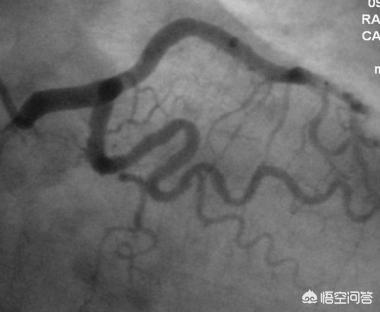

冠動脈疾患の核心は心筋細胞の虚血と低酸素症であり、心筋細胞の虚血と低酸素症の最も一般的な原因は冠動脈の動脈硬化による冠動脈狭窄である。冠動脈疾患の診断は、一般的に臨床診断の簡単な方法があり、活動に関連した心前圧のような痛みがあり、手のひらの大きさ程度で、数分から10分間安静にしていると緩和することができ、特に高血圧、高脂血症、糖尿病などの心血管危険因子を持つ患者は、冠動脈疾患の診断を直接臨床診断することができます。冠状動脈疾患の最終的な診断は、伝統的に最も古典的な方法は、冠状動脈CTAまたは冠状動脈造影の結果に頼ることであり、冠状動脈の狭窄の程度が50%以上に達すると、冠状動脈疾患の診断を確認することができます。

今後、血管内超音波検査などの新技術が開発されれば、人体への負担が少なく、より優れた検査法が登場することは間違いないが、今のところ、冠動脈疾患の診断と管理は、主に冠動脈造影検査に頼っているのが現状である。

ゴールドスタンダードは冠動脈造影で、スクリーニングには冠動脈造影CTを用いる。